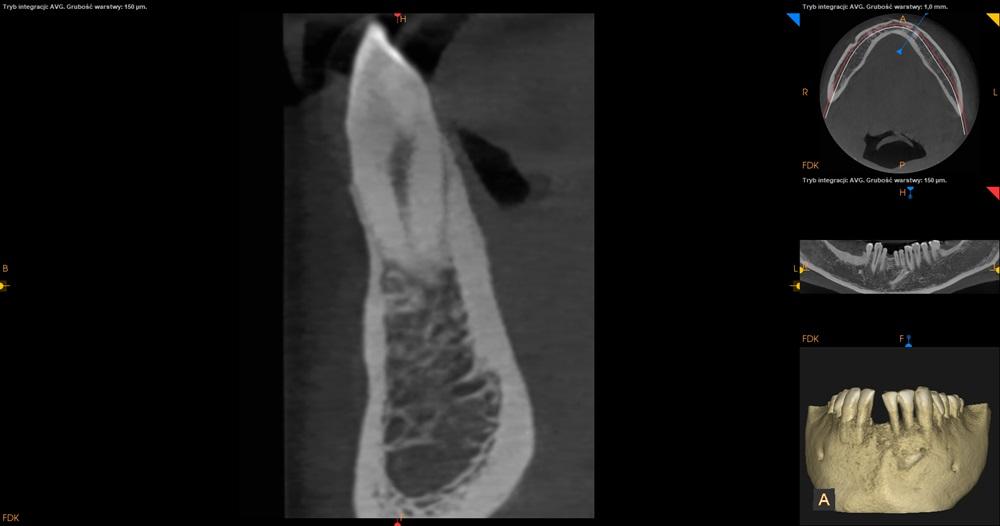

Tomografia CBCT żuchwa.

Ząb 41 – całkowicie zatrzymany. Położony skośnie, koroną skierowany w stronę mezjalną z przekroczeniem linii pośrodkowej. Korona zęba 41 położona po stronie przedsionkowej wierzchołków korzeni 33 i 32. Resorpcja korzeni niewidoczna. Wierzchołek korzenia zęba 41 lekko zagięty.